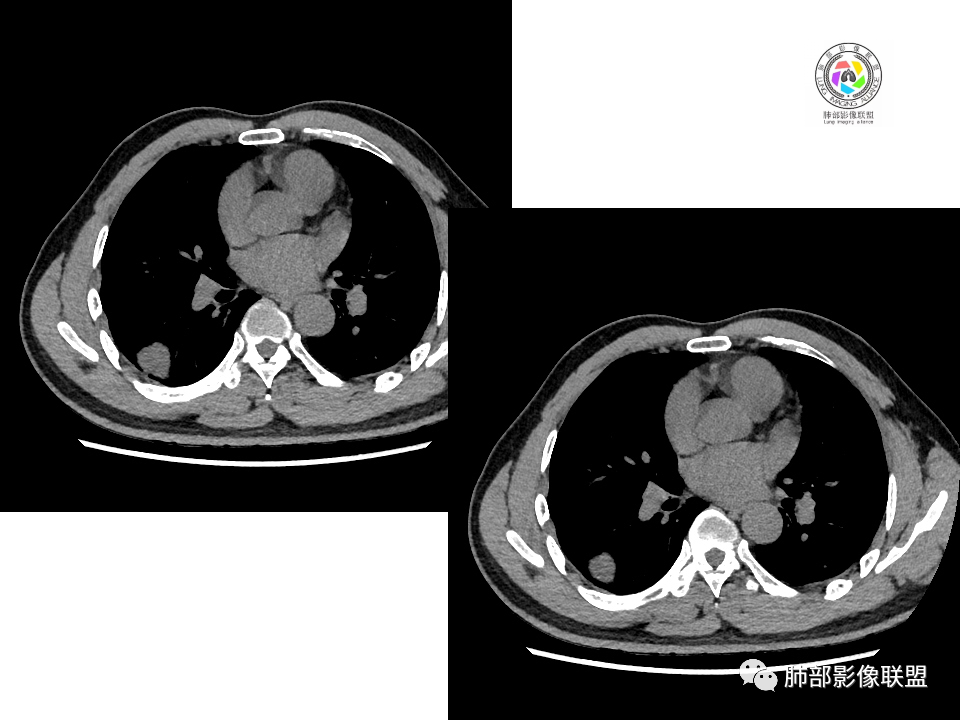

男性,49岁,体检发现,右肺下叶背段胸膜下见肿块,边界清楚,边缘光滑,胸膜下脂肪间隙存在,有分叶,无毛刺,均匀强化,内无坏死,右肺下叶血管束间不规则实性结节,边界清楚,无明显强化,中叶少许斑片状高密度影,纵隔未见明显增大淋巴结,考虑良性病变。

2.右肺下叶背段胸膜下块影,边界清楚光整,上下极见磨玻璃晕,未见明显分叶毛刺和棘状突起,未见胸膜凹陷或胸壁侵入。密度均匀,轻度不均匀强化。未见支气管进入。

3.右肺中叶外侧段胸膜下散在小片影,磨玻璃密度为主,边界不清,支气管相关。符合炎性特征!

4.右肺下叶基底段支气管血管束旁小结节影,边界清楚,强化不明显。注意,这结节在“遥远的”基底段。

右肺下叶占位,胸膜下,与胸膜关系密切;

密度均匀;糊墙,边缘膨隆为主;

部分血管推移。